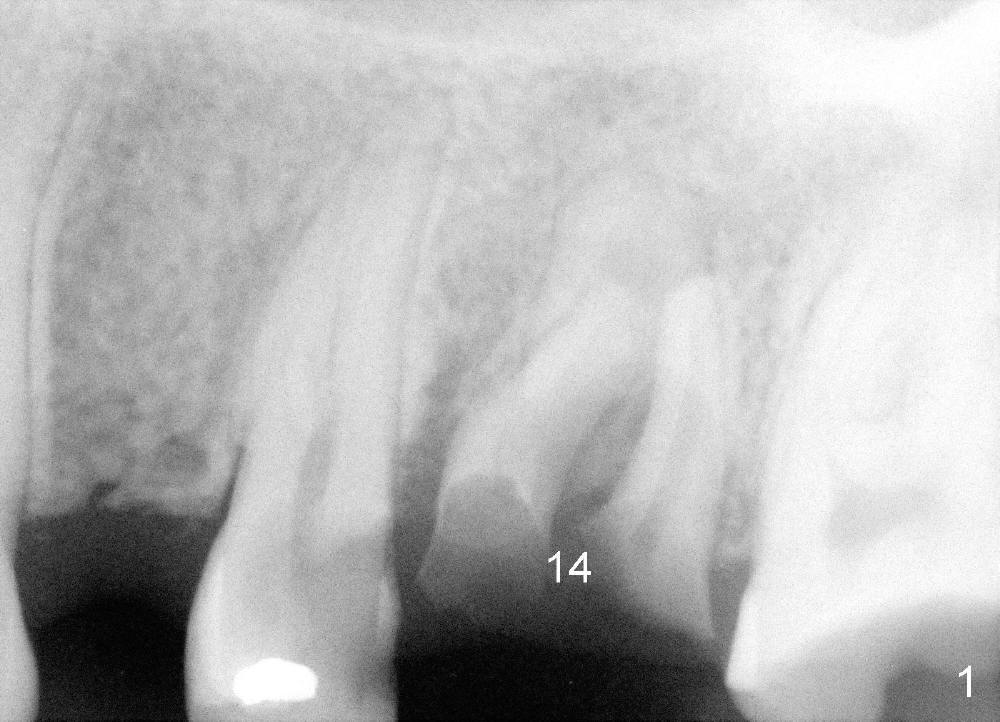

A 24-year-old man has poor dentition. The tooth #14 is beyond salvageable (Fig.1). The extraction socket is large (Fig.2). Dry socket develops 6 days post extraction without socket preservation (Fig.3).